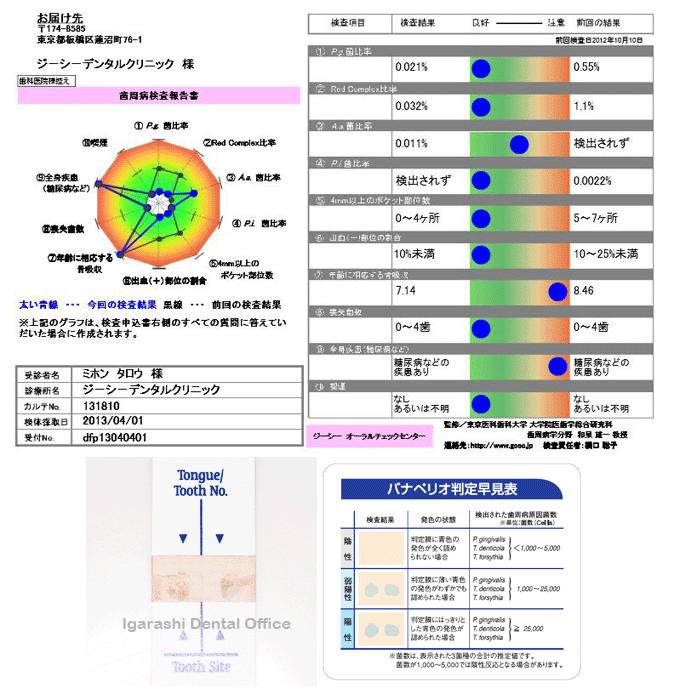

歯周病の症状は、外からは見えない歯茎の内部で進行します。また、歯周病は細菌による感染症ですが、その原因となる細菌には多くの種類があり、効果的な治療法や薬は細菌の種類によって異なります。 そのため、当院では科学的な検査を通じて原因を特定し、患者さん一人ひとりに最適な治療プログラムを策定しています。まずは、検査や治療方法についてご紹介します。

お伝えしているように、歯周病は、外見だけではその進行具合を判断することが非常に難しい病気です。そのため、当院では専用の器具や精密機器を活用して、科学的な検査を行い、病状を正確に診断します。

このアプローチにより、初期段階の歯周病も見逃すことなく、適切な治療が可能になります。

唾液の中には多くの細菌が含まれています。そのため、唾液検査を通じて、虫歯や歯周病のリスクを詳細に分析します。この検査により、虫歯や歯周病に対する患者さんの個々の傾向を明らかにし、それぞれの状態に最適な予防策や治療プランを策定することが可能です。また、口内環境の健康状態を評価し、特定のリスク要因を早期に特定します。